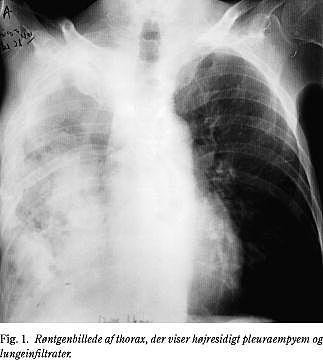

Den torakale actinomykose (ca. 15%) med pulmonal infektion som følge af aspiration viser sig som en langsomt progredierende proces, som både kan inddrage lungeparenkymet og pleura (Fig. 1). Patienterne har symptomer i form af brystsmerter, feber, vægttab og hoste. Ofte ses ingen specifikke radiologiske forandringer, og alle lungelapper kan være afficeret.